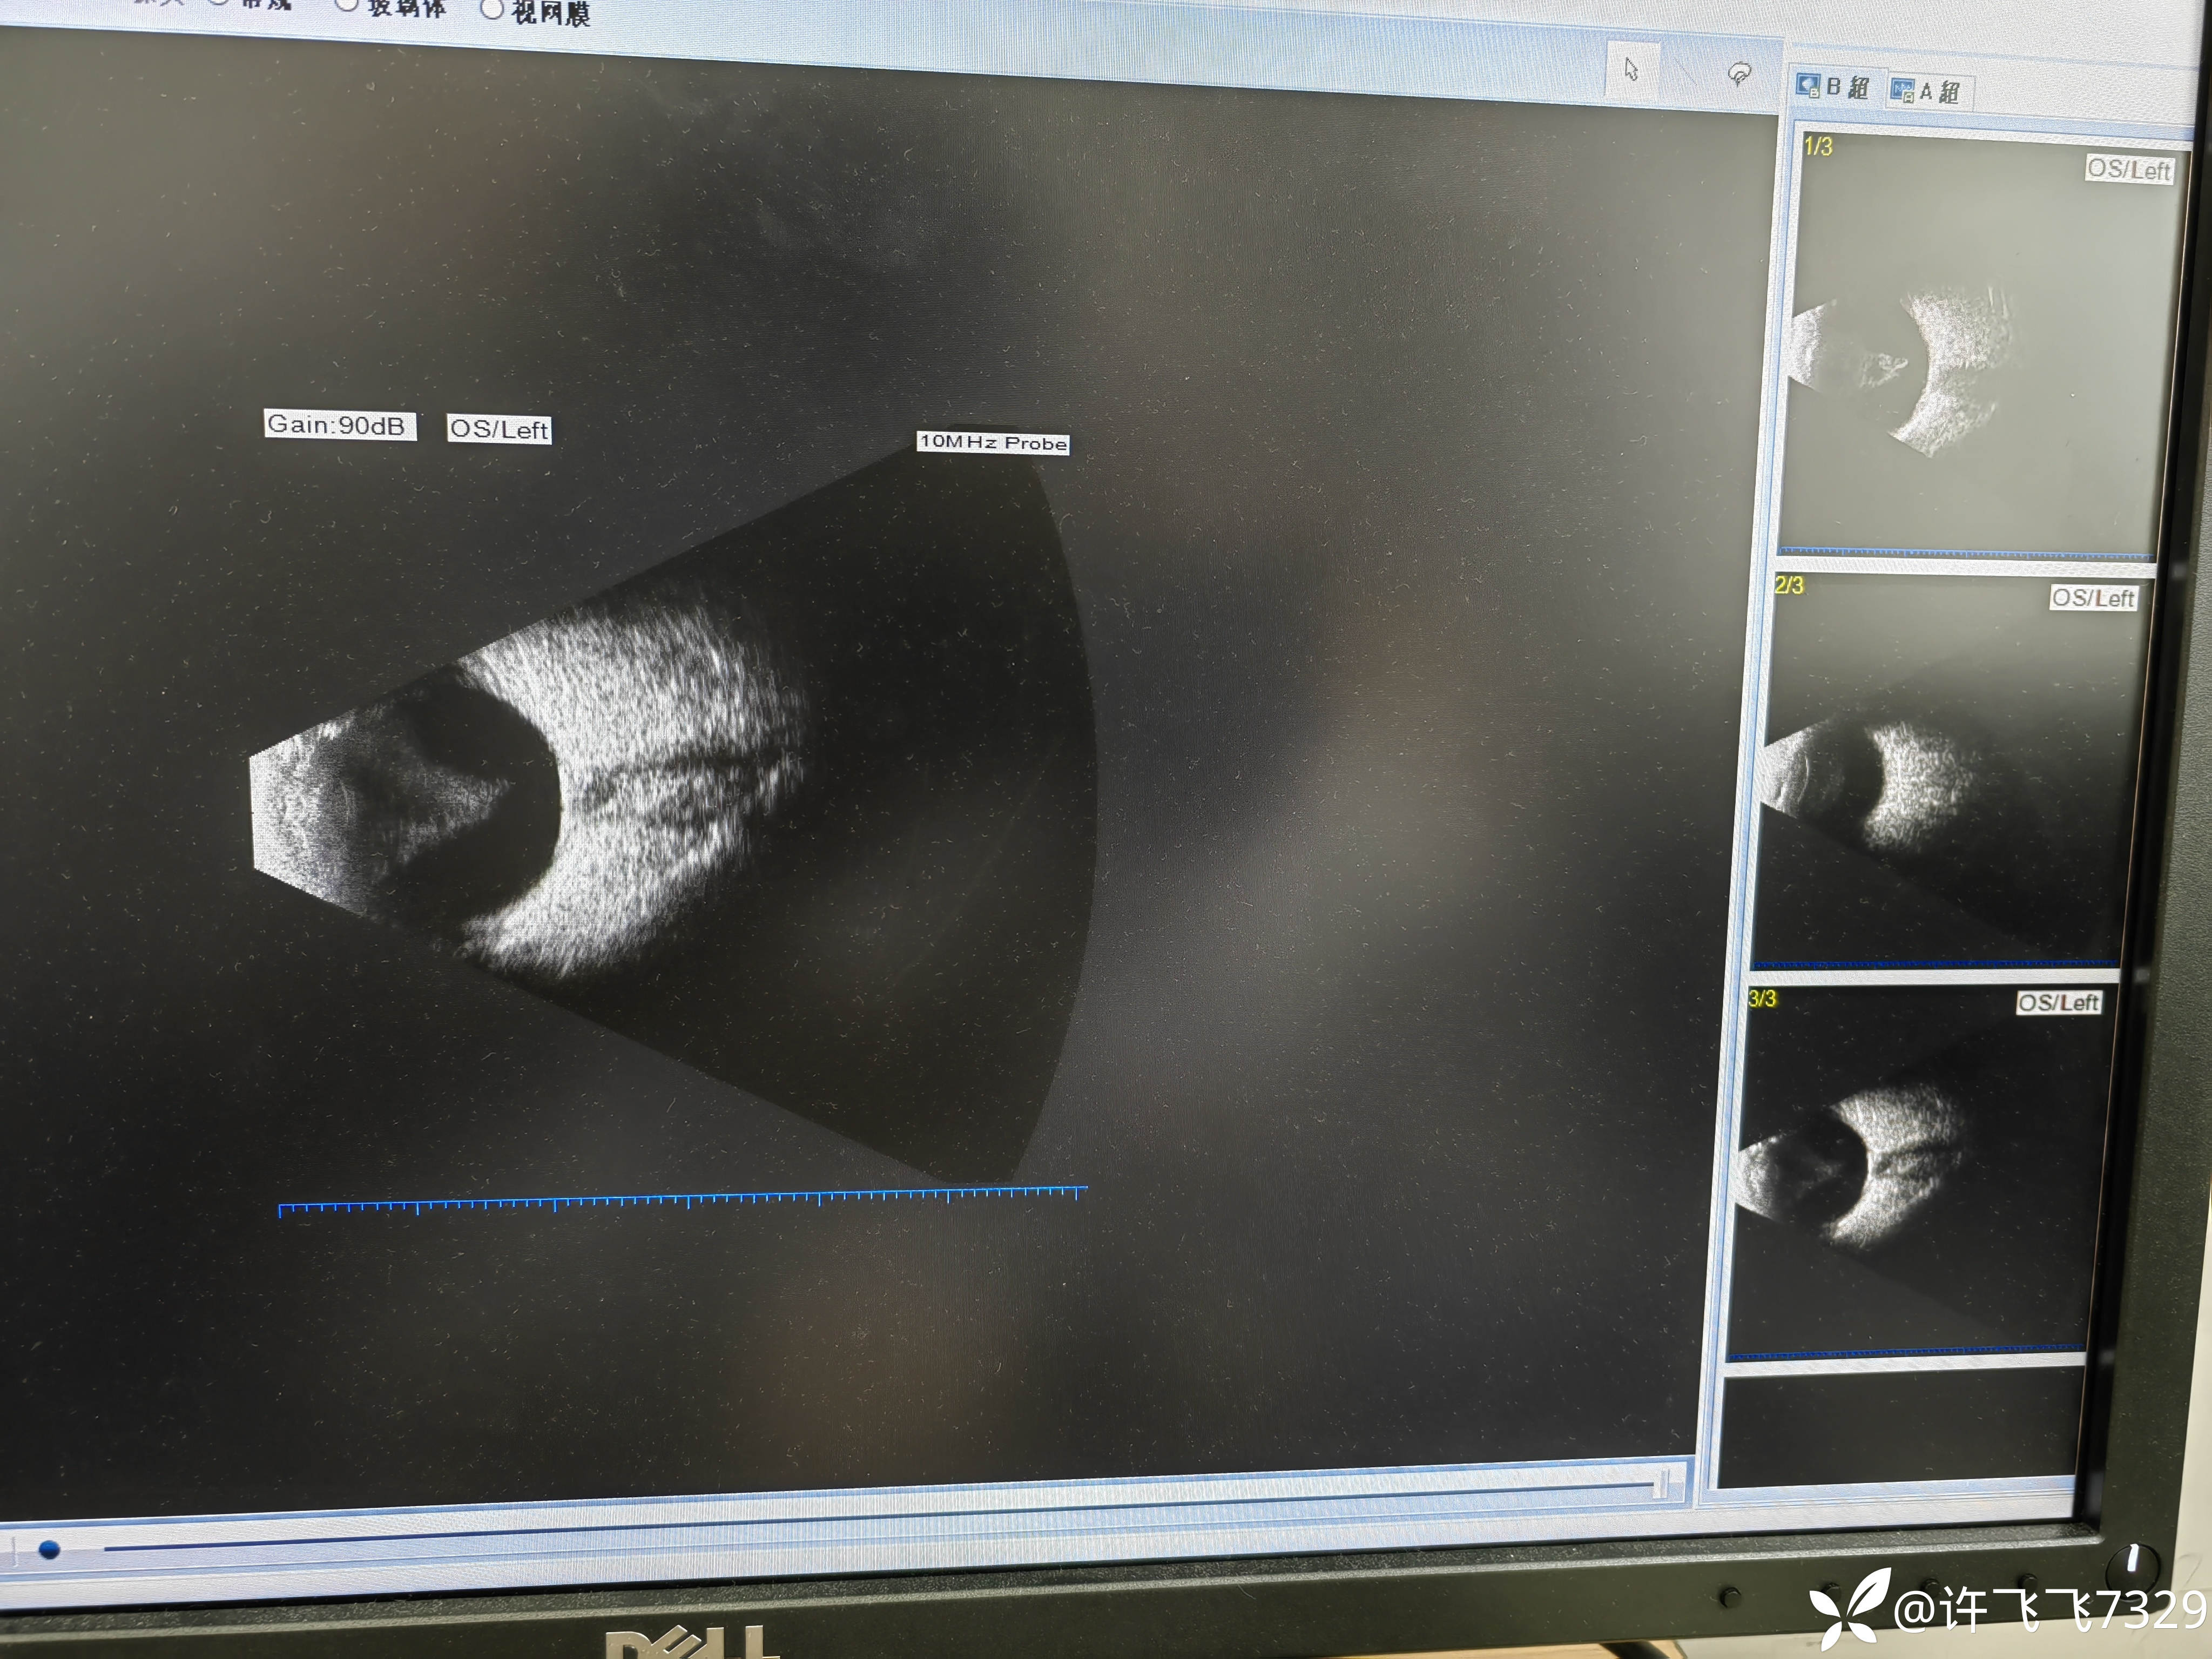

【患者信息】:85岁老年女性

【主诉】左眼视物不清十年余

【现病史及既往史】:左眼青光眼手术十年余,右眼青光眼

【临床诊断】:双眼老年性白内障,双眼青光眼

【治疗经过及结果】:初干眼科的小白,眼科各位大佬们,这B超里面是玻血吗?这是什么东西?